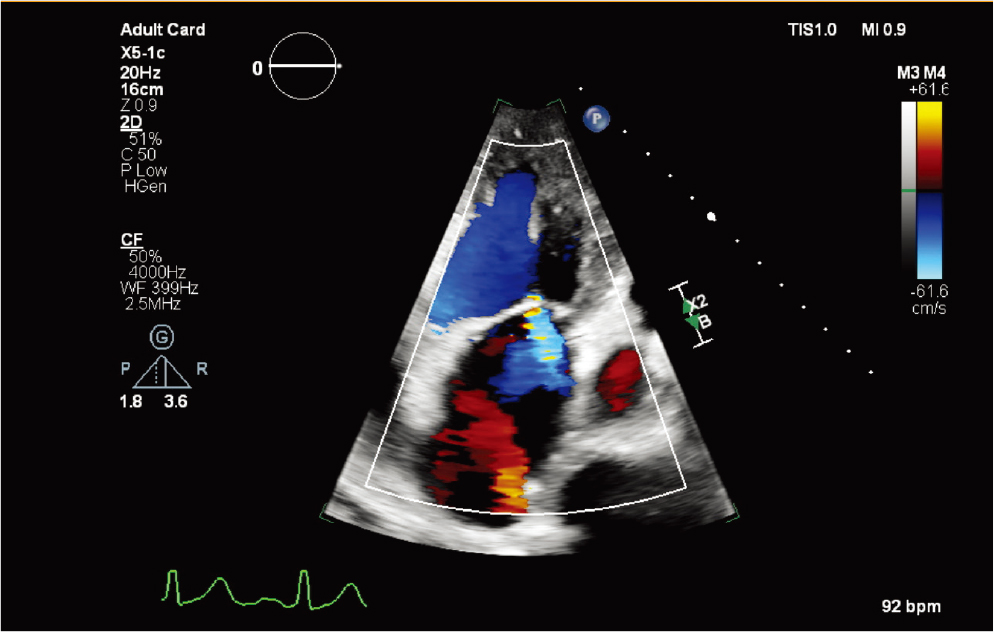

X5-1c探头

X5-1c 探头配备 nSight Plus,有助于优化 TTE 成像 |

X5-1c 探头肋下 xPlane 肺动脉图像 |

X5-1c 探头彩色多普勒二尖瓣返流(MR) |

X5-1c 磁共振 CW 多普勒探头 |

X5-1c t探头的动态心脏模型 |

X5-1c 探头进行自动节段性室壁运动评分指数 |